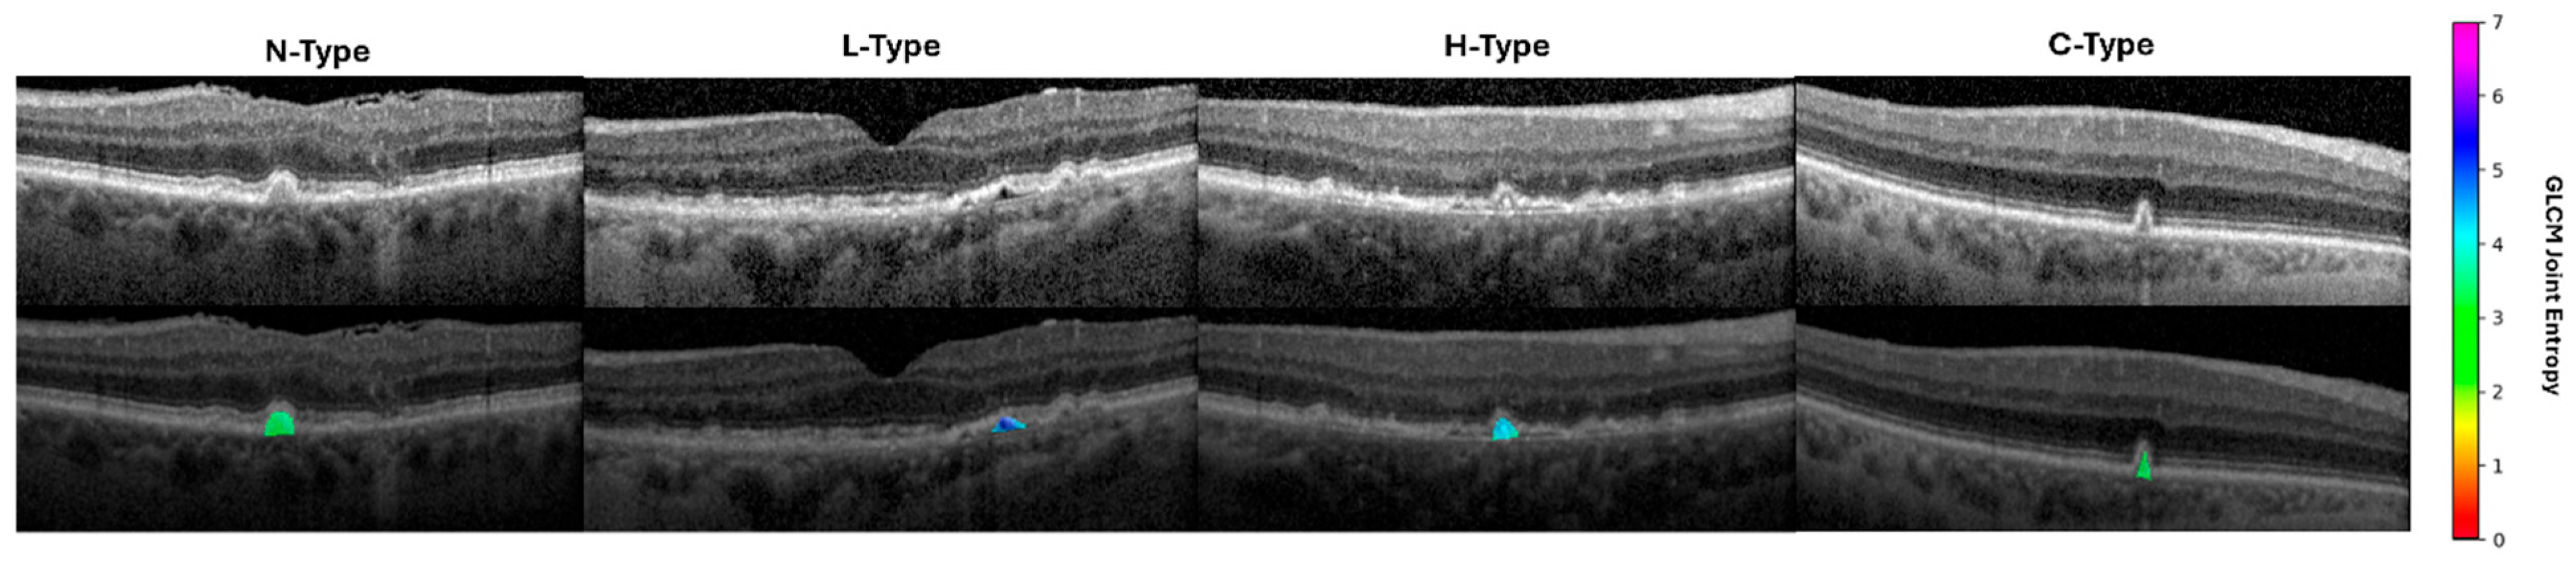

Figure 4. Visualization of a representative radiomic feature across drusen phenotypes. Heatmaps and color scale represent GLCM joint entropy value in the 10-pixel radius around each pixel within the druse. GLCM: gray level co-occurrence matrix.

To develop a dataset of drusen with ODS phenotypes for radiomic extraction, OCT B-scans were manually graded for the presence of ODSs using two independent graders with a final arbitrator, the same grading framework as Veerappan et al. [10]. A total of 104 N-type, 105 L-type, 101 H-type, and 129 C-type drusen were manually segmented from OCT scans of 75 patients from Cole Eye Institute (Cirrus scans, 31 patients) and Retina Consultants of Texas (Spectralis scans, 44 patients). ODSs were defined in a similar manner as described previously in the literature: L-type had a focal, well-circumscribed sub-volume of distinct hypo-reflectivity within the druse relative to the surrounding druse material, not contiguous with the RPE or BM and with size > 2 pixels; H-type had a focal, well-circumscribed sub-volume of distinct hyper-reflectivity within the druse relative to the surrounding druse material, not contiguous with the RPE or BM and size > 2 pixels; C-type had a conical shape—in contrast to the definition of Veerappan et al., debris criteria were not included, as very few conical-shaped drusen with debris were found in this dataset—a notable difference not previously reported; N-type was defined as a druse of homogeneous reflectivity [10]. Pixel-level thresholds were used for consistency with Veerappan et al., as well as for consistency across scans as image resolution was on the order of microns per pixel. Representative examples are shown in Figure 2. Although split reflective drusen were identified by Veerappan et al., only one druse of this type was found in these datasets, so this subtype was excluded from the analysis.

Radiomic features classified ODS phenotypes with AUC = 0.90 +/− 0.03 for N-Type, 0.90 +/− 0.03 for L-Type, 0.86 +/− 0.05 for H-Type, and 0.94 +/− 0.03 for C-Type (Figure 3). The most important radiomic features included the drusen pixel intensity, texture, and shape (Table 1, Table 2, Table 3 and Table 4, Figure 4). Six important features were found for L-type ODSs, fifteen were found for H-type, four were found for C-type, and five were found for N-type (Table 1, Table 2, Table 3 and Table 4). L-type ODSs were characterized by texture and pixel intensity features: high NGTDM contrast, low 90th percentile pixel intensity, high GLSZM gray level variance, low kurtosis, and low pixel intensity uniformity (Table 1). H-type ODSs were characterized by texture and pixel intensity features, as well as shape elongation: high GLCM sum entropy, low radiomic elongation, high pixel intensity energy, high GLCM sum squares, high maximum pixel intensity, high GLCM autocorrelation, high GLCM joint entropy, low GLSZM size zone non-uniformity normalized, high pixel intensity total energy, high GLCM cluster tendency, high pixel intensity entropy, high GLDM dependence entropy, high GLDM high gray level emphasis, high GLCM correlation, and high pixel intensity range (Table 2). C-type ODSs were characterized by texture and shape features: low GLCM correlation, low minor axis length, low sphericity, and low GLCM sum entropy (Table 3). N-type ODSs were characterized by texture, shape, and pixel intensity features: high GLSZM large area emphasis, high sphericity, low pixel intensity entropy, low NGTDM contrast, and high GLSZM zone variance (Table 4).